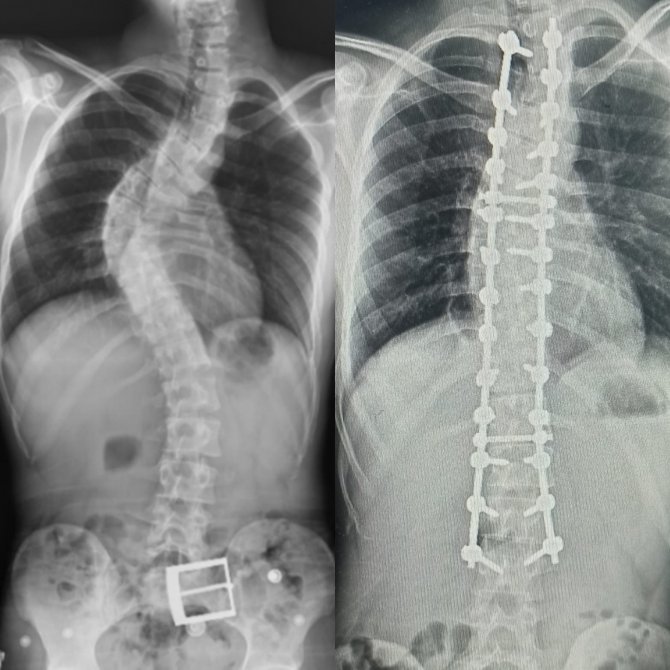

Yapılan muayene ve incelemeler sonucu hastada 73 derece skolyoz (omurga eğriliği) ve kifoz (kamburluk) tespit edilerek Ahmet Akan'a ameliyat önerildi. Samsun Üniversitesi Tıp Fakültesi Ortopedi ve Travmatoloji Anabilim Dalı Öğretim Üyelerinden Dr. Öğr. Üyesi Ömer Bozduman, deneyimli ameliyat ve anestezi ekibi eşliğinde görev yaptığı Samsun Eğitim ve Araştırma Hastanesi'nde 7 saat süren başarılı bir skolyoz ameliyatı gerçekleştirdi.

Hasta ile ilgili bilgi veren Dr. Öğretim Üyesi Ömer Bozduman, "Hastamız artan sırt ağrıları ve omurga eğriliğinin ilerlemesi şikâyetiyle kliniğimize başvurdu. İnceleme ve değerlendirmelerimiz sonucu ameliyat kararı verdik. 7 saat süren skolyoz ameliyatını takiben 12 saat sonra hastamız kaldırılıp yürütüldü. Ameliyat sonrası nörolojik olarak hiçbir sorunu yok. Eğriliği tamamen düzeldi, boyu uzadı. Şu an kendisi yürüyüp gezebiliyor. Hastayı 5 gün sonra taburcu edip evine gönderiyoruz. Her ameliyatta olduğu gibi skolyoz ameliyatlarında da ekip çalışması çok önemlidir. Uzun süren bu ameliyatı, hastanemizin özverili ameliyat ve servis hemşireleri ve deneyimli anestezi ekibi ile gerçekleştirdik" dedi.